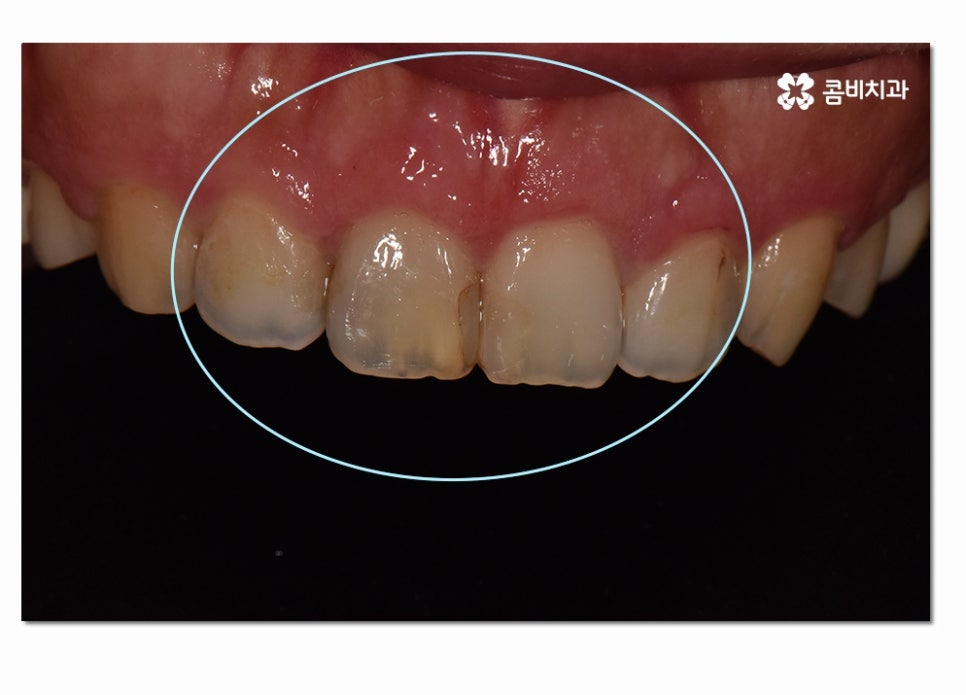

위에 보시는 것처럼 치은절제술 치료가 잘 이뤄지고 잇몸이 다시

건강한 색과 모양으로 회복된 것을 느낄 수 있는데요.

치주 질환은 심각성에 비해서 치은염이 발생한 상태에서도

크게 통증을 못 느끼시는 분들도 많기 때문에

대수롭지 않게 여기다가 나중에 치아를 잃을 정도로

심각한 문제로 이어지는 경우를 많이 볼 수 있어요.